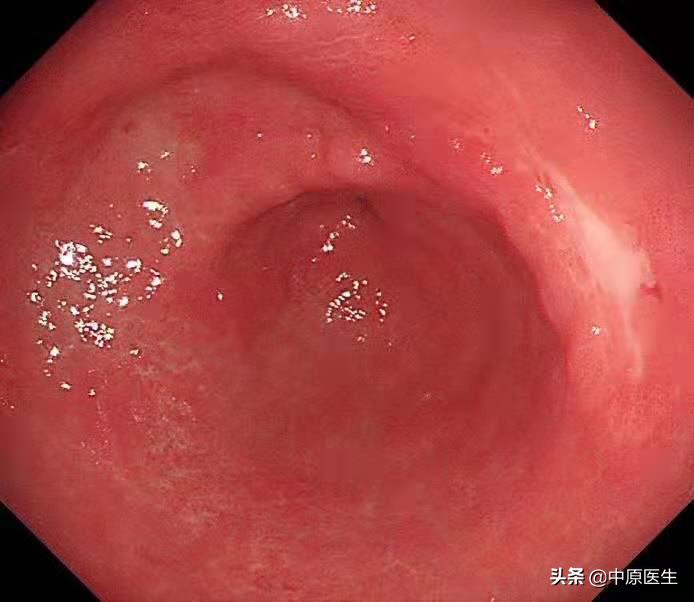

胃镜安排在上周五,*操我**作胃镜,顺利通过食管,准确到达了胃内,果然在胃角中间的地方,发现了一个溃疡,我的心头一紧,这可不像是早期胃癌呀!

我接着按照程序仔细检查每一个角落,结果在胃角的前壁、胃窦后壁又分别发现了一个溃疡,

我心中暗暗松了一口气,因为根据既往的经验,多发溃疡,良性可能性大,或许是地方医院的病理结果不准确。

通常,在胃镜检查时发现溃疡病变,需要做良恶性鉴别,内镜下鉴别良性和恶性溃疡(也就是通常说的胃癌)需要从以下几个方面考虑,第一、病变的大小,大的溃疡恶性的可能性大。第二、形状,恶性溃疡往往形状不规则;第三、恶性溃疡的底部往往凹凸不平;第四、恶性溃疡表面的苔往往污秽(很脏);第五、恶性溃疡的边缘多伴有结节样隆起,反之,则良性可能大。

这个患者的溃疡多发,不算太大,并且表面的苔很干净,底部也算平坦,尤其是新发现的两个溃疡,从这几个条件来看,似乎良性可能性大。但是,我还是不放心。我现在只是用了白光检查,为什么不选择窄带光,放大检查?虽然麻烦一点,但是,可以看到更多细节!于是,我打开NBI模式,并且使用变焦(俗称放大,可以达到和显微镜下看类似的效果),再仔细地对每一处病变进行了观察,结果竟然发现,虽然范围很小,尤其是胃窦处的溃疡,不超过2个毫米的范围内我都发现了腺管缺失和血管异常扩张的地方,这往往提示病变有可能已经癌变,在放大镜的引导下,我对病变进行了精准活检。